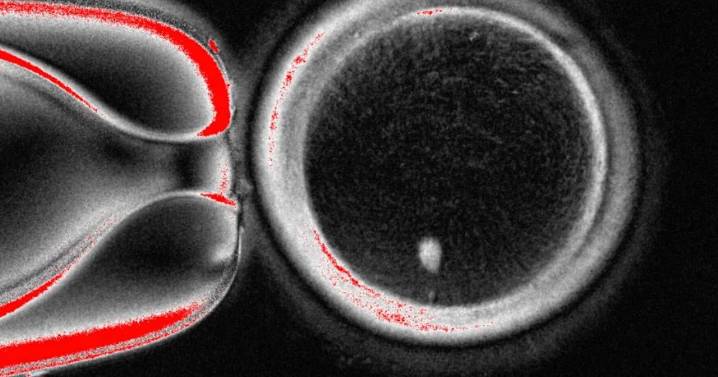

WASHINGTON (AP) — Científicos de Oregón utilizaron células de piel humana para crear óvulos fertilizables, un paso en la búsqueda de desarrollar óvulos o espermatozoides cultivados en laboratorio para ayudar a las personas a concebir en el futuro.

Sin embargo, el experimento resultó en anomalías en los cromosomas, lo que llevó al equipo de la Universidad de Salud y Ciencia de Oregon (o Oregon Health & Science University, OHSU) a advertir que podría tomar una década de investigación adicional antes de que tal técnica esté lista para ensayos en personas.

El trabajo publicado el martes en Nature Communications puede ofrecer lecciones mientras los científicos intentan aprender a crear óvulos y espermatozoides en un laboratorio para personas infértiles o para ayudar a parejas del mismo sexo a